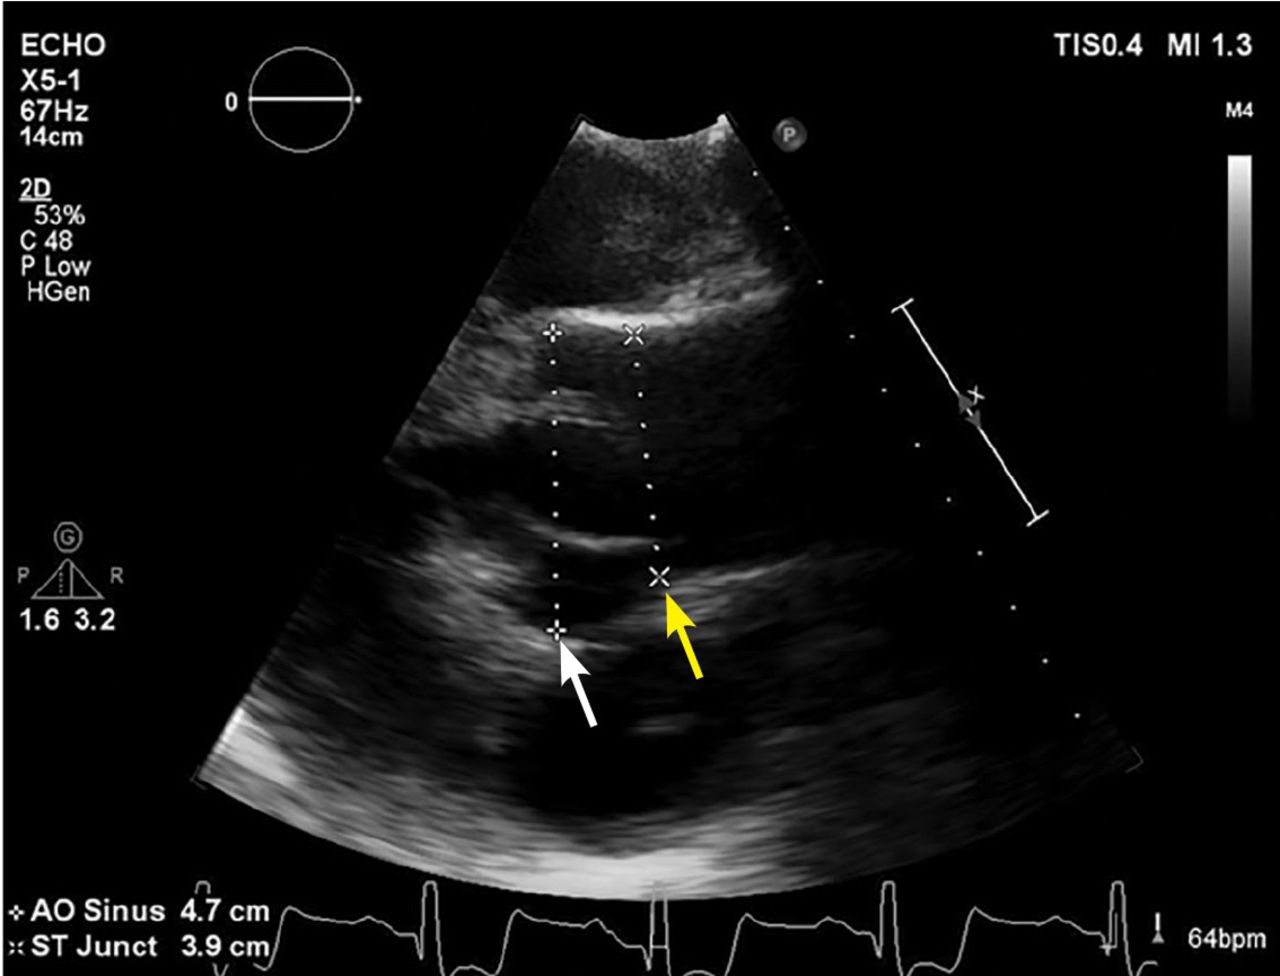

Echocardiographic image of an aneurysmal aortic root (white arrow) that tapers to normal dimensions at the sinotubular junction (yellow arrow) and ascending aorta. See videos (this image and a bicuspid aortic valve).

TAA can be diagnosed with several imaging tests, each with advantages and disadvantages (Table 4).12 Most commonly used in its diagnosis and follow-up are transthoracic echocardiography (Figure 2), cardiac-gated computed tomographic angiography (CTA), and MRI (Figure 3). Transesophageal echocardiography is not routinely used in diagnosing TAA but is invaluable during surgery to assess aortic valve function and immediate results of aortic repair.